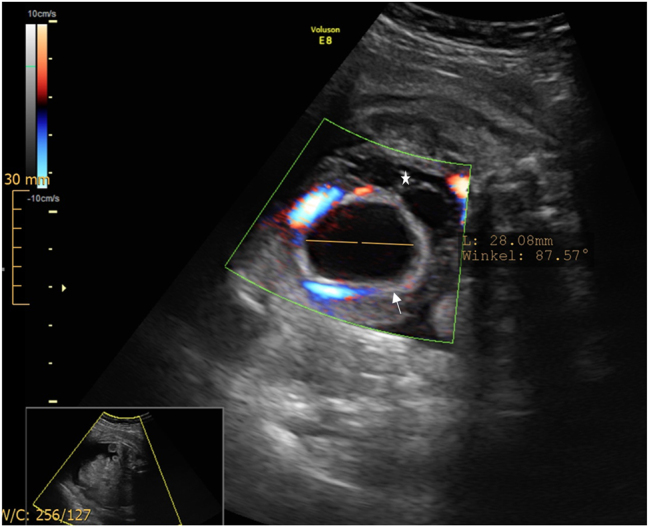

Case presentation: A 18-year old first Gravida at 31 weeks of gestation developed a severe sepsis with progressive hypoxic lung failure and need for intubation. During the ICU-treatment, several opioids were administered for sedation and pain relief. Four days after induction of opioid treatment the ultrasound revealed a decompressed fetal bladder, hematoma and significant ascites. Fetal bladder rupture with urinary ascites was suspected. A caesarean section was performed at 33 weeks of gestation due to massive fetal urinary ascites, fetal deterioration and imminent abdominal compartment syndrome. Adequate ventilation and circulation could only be established after percutaneous drainage of 350 mL of abdominal fluid, that was confirmed to be urine. A defect of the bladder was confirmed by ultrasound. On the fifth day of life, the bladder was closed surgically by pediatric surgery.